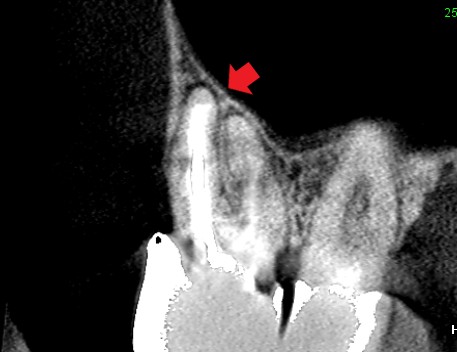

矢印の先が根の先にできている膿です。膿は上顎洞という副鼻腔に接しています。ここから上顎洞に炎症が波及したり、膿が上顎洞にあふれ出てもおかしくない状態です。

精密再根管治療完了6ヶ月後のCT画像です。

根の先にあった膿が消えています。ここから、精密被せ物治療に入ることができるようになりました。